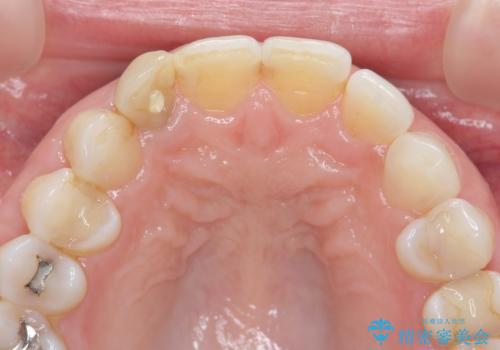

X線検査の結果、失活(感染根管)であることが判明したので、感染根管治療後セラミック補綴を計画します。

セラミック治療を行う前にきっちりと根管治療を行うことが長期的に持つ可能性を高めます。

- 天然歯を削ります

- 硬い素材は天然歯を傷つけてしまう場合があります

- かみ合わせや歯ぎしりが強すぎる方はセラミックが割れてしまう可能性があります